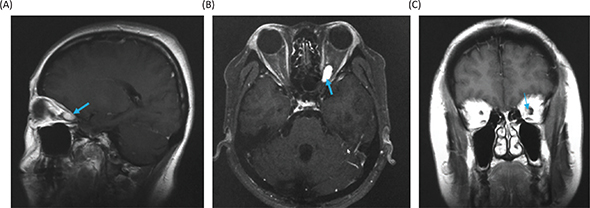

Figure 5. Gadolinium-enhanced magnetic resonance images at 18 months after the stereotactic radiosurgery. (A) Sagittal image. (B) Axial image. (C) Coronal image.

The differential diagnoses for the tumor include optic glioma, optic sheath meningioma, optic nerve schwannoma and optic nerve hemangioblastoma. Among them, since the patient is a VHL patient, the most probable diagnosis was thought to be an optic nerve hemangioblastoma. Therefore, we made a decision to treat the tumor with stereotactic radiosurgery. At Shonan Fujisawa Tokushukai Hospital, the stereotactic radiosurgery was prescribed with the dose being 39 Gy/13 fractions using Novalis. The planning target volume was set at 0.7 mL, and D95 (95% of standard irradiation volume) was set at 35 Gy/13 fractions. The patient completely lost her vision after the radiosurgery. Eighteen months after the radiosurgery, the tumor volume slightly decreased (Figure 5), but her vision has been still lost. The consent to publish the case has been given by the patient.